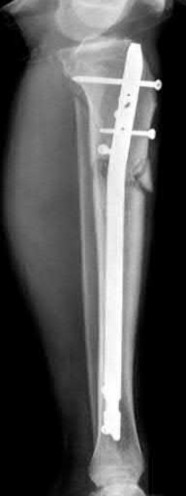

A 28-year-old male sustains a closed comminuted tibial shaft fracture.

Two hours post-injury, he develops severe leg pain unyielding to narcotics. His blood pressure is 120/80 mmHg. Intracompartmental pressure monitoring is performed. Based on current guidelines, which measurement dictates an emergent 4-compartment fasciotomy?

Explanation

Acute compartment syndrome is classically defined by tissue hypoperfusion. The absolute compartment pressure is less reliable than the differential pressure (Delta P). A Delta P (Diastolic Blood Pressure minus Compartment Pressure) of less than 30 mmHg is an absolute indication for emergency fasciotomy, as capillary perfusion gradient is lost when tissue pressure approaches the diastolic pressure.